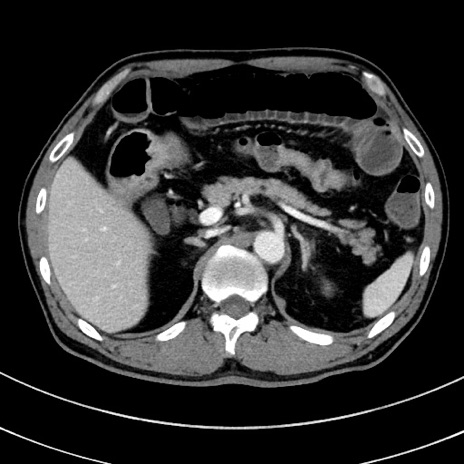

症例8(横断像)

【症例】 60歳代男性

【主訴】 黒色吐物

【現病歴】 4日前から嘔気自覚、2日前の朝食後にも嘔気あり、自分で手で嘔吐反射起こし嘔吐したところ血が混ざっていたため受診。

【既往歴】 5年前汎発性腹膜炎を伴う急性虫垂炎で手術、高血圧、前立腺肥大症、高脂血症

【身体所見】 腹部正中に手術癩痕あり 腹部平坦・軟圧痛なし膨満感あり

【データ】WBC 8400、CRP 4.54